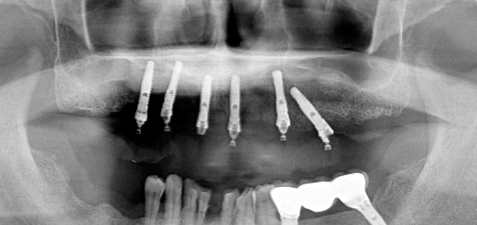

中途半端に悪い歯を残すと、後々治療が大変になるので思い切ってすべての歯を抜歯します

術直後の写真です

オールオン6本のインプラントをいれました

初期固定もよかったので即時荷重をおこなっています